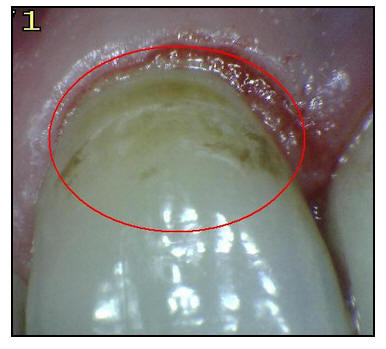

En la imagen

se muestra en color rojo las áreas de estancamiento de la placa

bacteriana en las superficies oclusales, espacios interproximales y los cuellos dentarios. Si la placa

no es

eliminada períodicamente las posibilidad de una lesión cariosa

es alta.

No

obstante, examinando el diente extraído después de seco y limpio, puede observarse sin dificultad una pequeña región

blanca sobre la superficie proximal (Ovalo en color rojo) Esta es la mancha blanca

que representa la más incipiente evidencia macroscópica de

caries; la superficie del esmalte que cubre esta lesión está

intacta y correctamente mineralizada, sin que pueda detectarse

diferencia al tacto con una sonda de exploración.